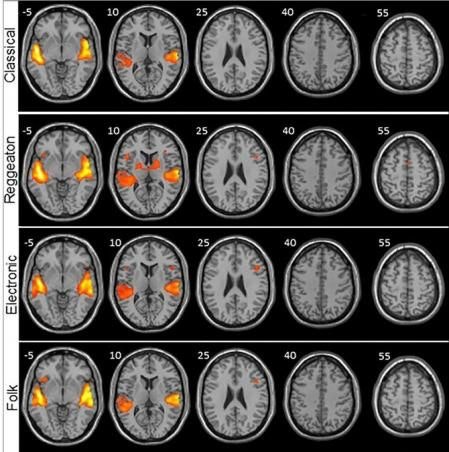

Por último, los investigadores analizaron anatómicamente el cerebro de cada participante mediante una herramienta que denominan la señal BOLD, que consiste en ver las áreas del cerebro que necesitan más oxígeno (que es lo que sucede cuando se activan) y a través de un software las fueron coloreando dependiendo de la intensidad que presentaran.

Como veremos en la imagen compartida por el estudio, la música electrónica y el folk también generan una considerable actividad cerebral. La pregunta aquí es ¿dónde quedó el rock?